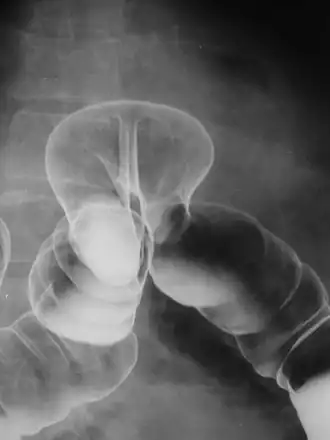

Radiograph of a barium enema displaying a colonic herniation.

A lower gastrointestinal series is a medical procedure used to examine and diagnose problems with the human colon of the large intestine. Radiographs (X-ray pictures) are taken while barium sulfate, a radiocontrast agent, fills the colon via an enema through the rectum.

Barium enemas are most commonly used to check bowel health; they can help diagnose and evaluate the extent of inflammatory bowel diseases such as ulcerative colitis and Crohn's disease. Polyps can be seen, though not removed during the exam like with a colonoscopy—they may be cancerous. Other problems such as diverticulosis (small pouches formed on the colon wall that can become inflamed) and intussusception can be found (and in certain cases the test itself can treat intussusception). An acute appendicitis or twisted loop of the bowel may also be seen. If the picture is normal a functional cause such as irritable bowel syndrome (IBS) may be considered.